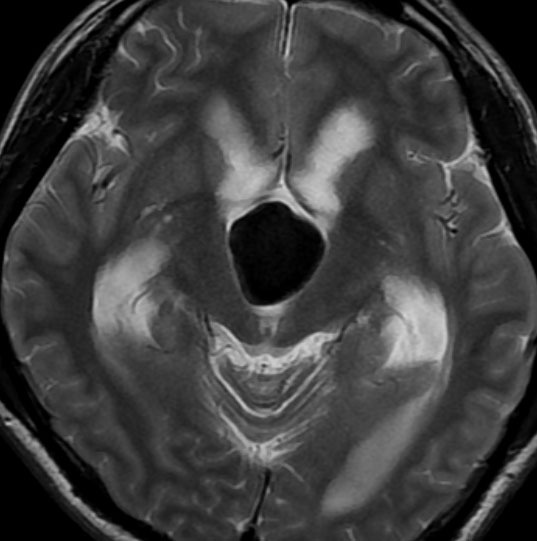

典型的な神経腸嚢胞 neurenteric cyst

左のT2強調画像で等信号,中のT2*で高信号,右はCISS画像です。

T1強調画像では,のう胞周囲の高信号の部分は半固体で,中心部の高信号はドロドロの粘液でした。基本的にガドリニウム増強はされません。まれに薄い膜状に一部が増強されることがあります。

境界明瞭は袋状の腫瘍です。椎骨動脈や脳底動脈を包み込むようにふくらんでいます。